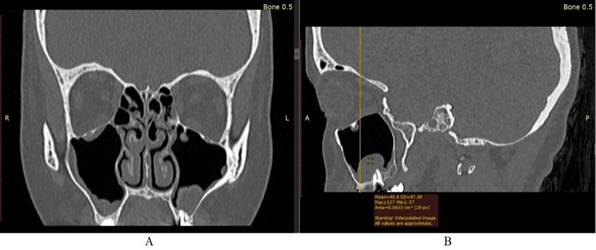

КТ-признаками острого гайморита являются снижение воздушности околоносовых пазух в результате отека слизистой оболочки и/или экссудата в полости пазухи. Горизонтальный уровень жидкости свидетельствует об экссудате в полости пазухи. КТ-признаками хронического гайморита является снижение воздушности околоносовых пазух со значительным и неравномерным утолщением слизистой оболочки из-за грануляций и полипозных разрастаний (рис. 2, 3).

/Alikariyev.files/image002.jpg)

Рисунок 2. Женщина, 58 лет. Снижение воздушности гайморовых пазух с утолщением слизистой оболочки на КТ: A- в сагиттальной проекции; B- во фронтальной проекции; С- в аксиальной проекции.